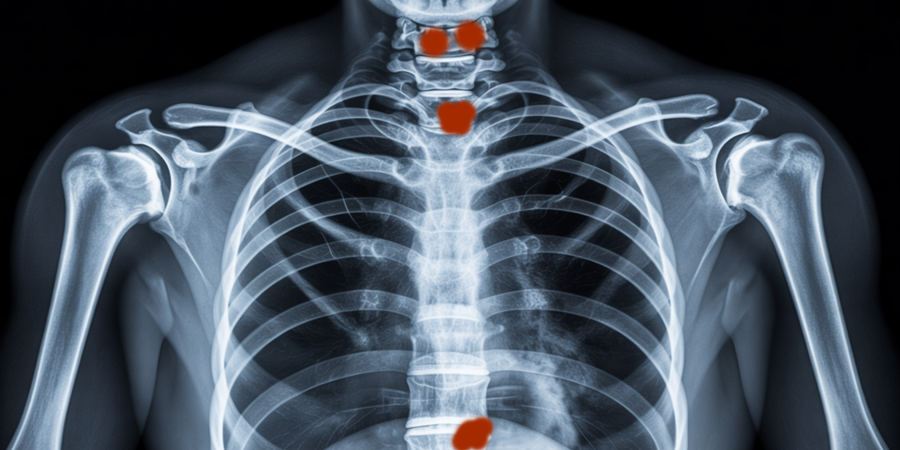

Imagem de ressonância evidenciando lesão única sugestiva de plasmocitoma ósseo solitário, diagnóstico diferencial do mieloma múltiplo./Ilustração Cortesia Editorial Ideia

O plasmocitoma solitário é uma neoplasia rara de plasmócitos, caracterizada pela presença de uma única lesão tumoral, seja em osso (plasmocitoma ósseo solitário - POS) ou em tecidos moles (plasmocitoma extramedular - PEM). Sua distinção precisa do mieloma múltiplo é fundamental, que os tratamentos e prognósticos são distintos.

• POS: Lesão única no esqueleto axial, como vértebras, costelas ou pelve.